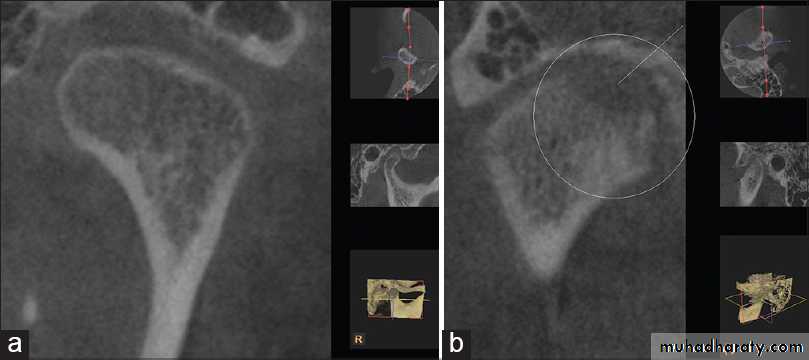

13Ankylosis

It is the union of two articulating surfaces of temporomandibular joint with fibrous or bone tissue leading to immobility or decreased mobilityDr. Mohammed Amjed Alsaegh, 2021

Before Completion of Growth

Destruction of the condyle and absence of proper function produces• Typical 'bird facies'

• Micrognathia

• Restricted somatic growth

• Malocclusion

• Dental caries

• Periodontal diseases

• Psychological trauma

• Restricted diet

• Antegonial notching and angular exostoses as a result of bone apposition beneath the pterygo-massetric sling.